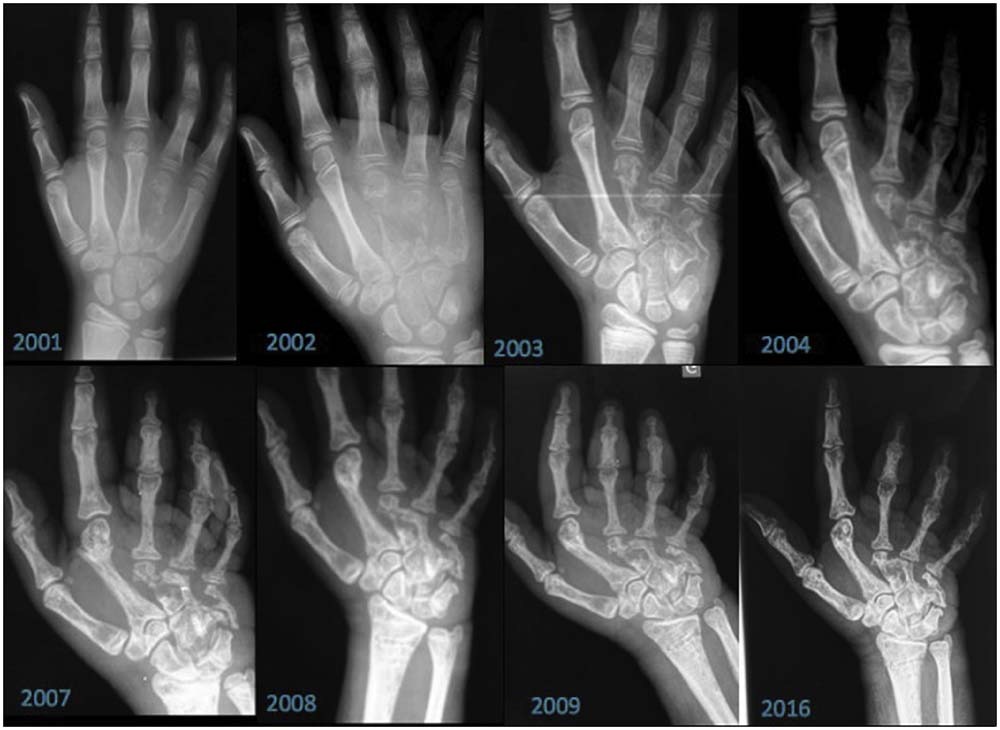

A imagem abaixo foi retirada do artigo “Gorham-Stout Disease: Hand Involvement in an 8-Year-Old Child” e mostra radiografias da mão esquerda entre 2001 e 2016, revelando osteólise progressiva e maciça do quarto metacarpo e dos ossos contíguos. Ou seja, a perda gradual e intensa do tecido ósseo, fazendo com que parte do osso desapareça nas imagens.

(Imagens utilizadas apenas para fins educativos e ilustrativos. A CORTS não realiza diagnóstico a partir de imagens publicadas neste blog.)